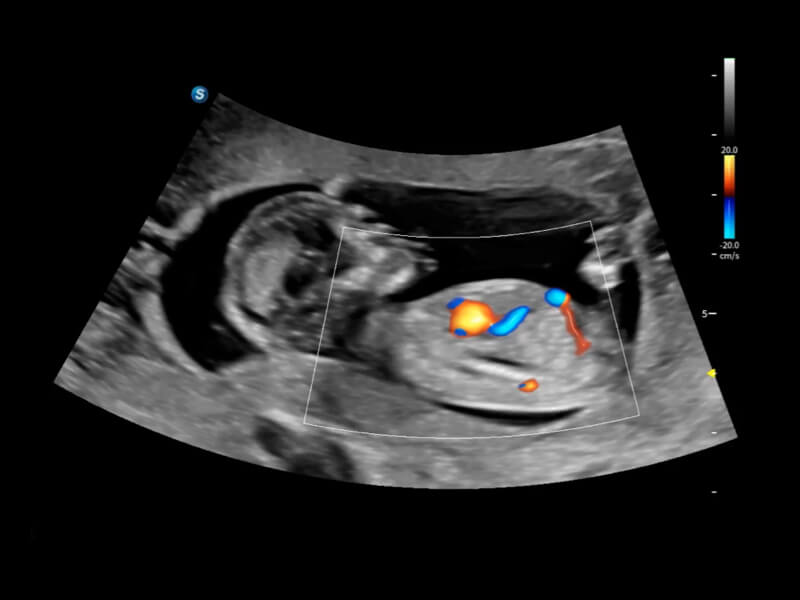

細(xì)微血流 纖毫畢現(xiàn)

豐富的血流動(dòng)力學(xué)檢測(cè)技術(shù),可在不同醫(yī)療場(chǎng)景中高效捕捉血流信號(hào),助力臨床診療。

• FHR 高幀率血流成像

在傳統(tǒng)血流的基礎(chǔ)上優(yōu)化掃查和算法策略,能夠更好的抑制組織信息,提煉紅細(xì)胞運(yùn)動(dòng)信息,得到更高幀頻,高靈敏度和分辨率的血流信號(hào),還原更真實(shí)的血流動(dòng)力學(xué)。

• Bright Flow立體血流成像

通過光照模型,使二維血流顯示出立體的效果,增加血流的敏感性、成束性,減少外溢??梢院推渌煌难骷夹g(shù)聯(lián)合使用,融合不同技術(shù)的優(yōu)勢(shì)。輕松應(yīng)對(duì)微小血管,增強(qiáng)血流的立體效果,提升視覺敏感性。